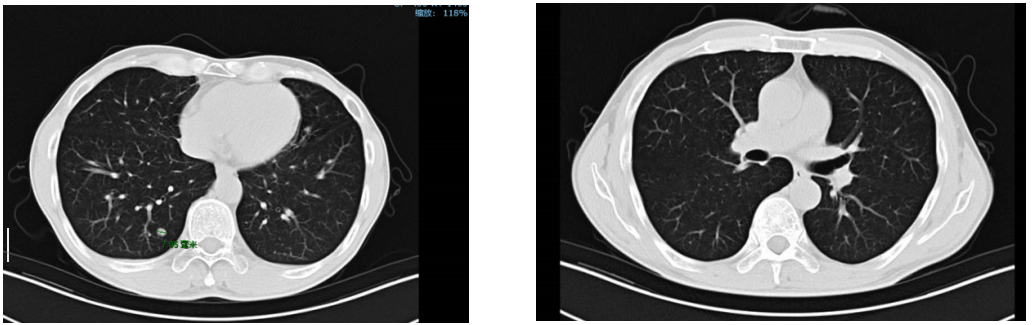

经影像学评估后,患者肝脏、双肺、颈部淋巴结无进展。

复查:2020.4复查颈部CT及全腹部+盆腔MR大致同前,脑MR示病变较前明显缩小,评估PR。

2020年11月4日复查颈部胸腹盆CT大致同前,脑转移灶明显缩小,继续赫赛汀联合希罗达维持治疗。